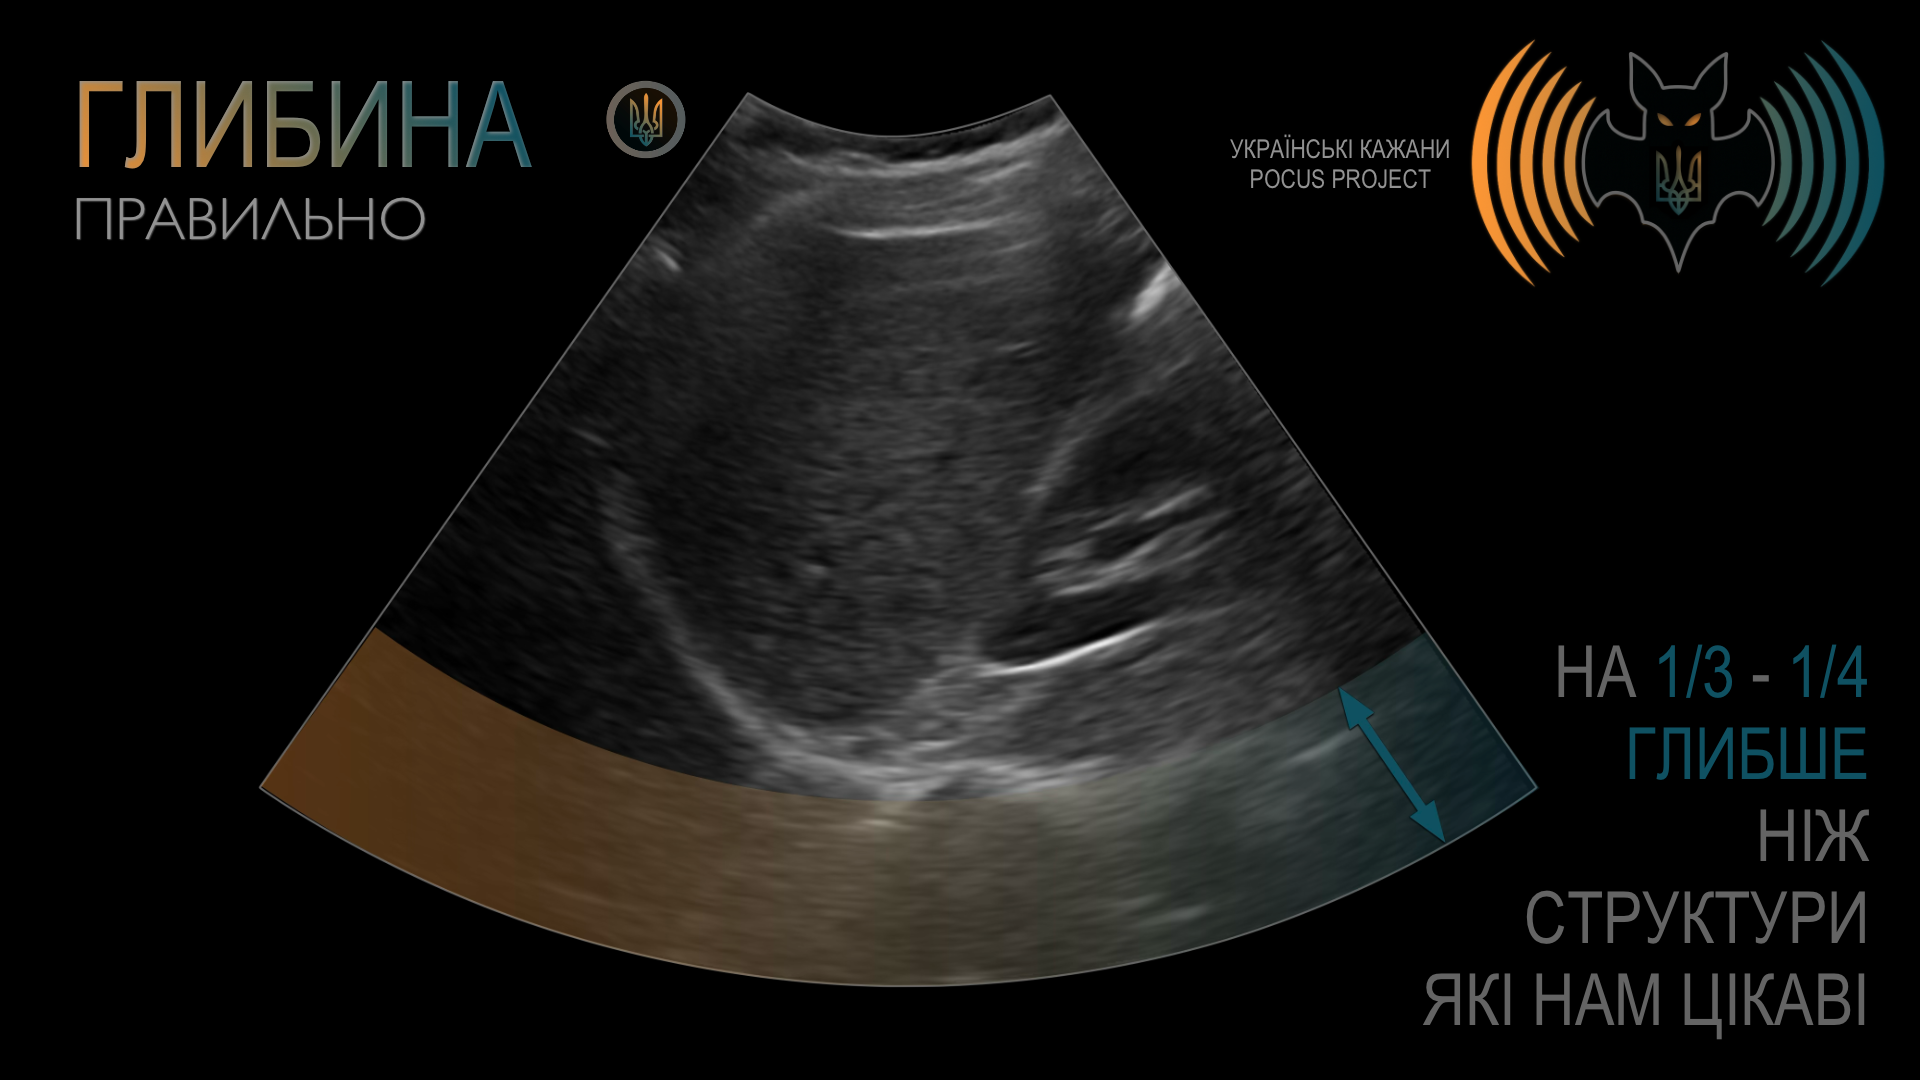

ГЛИБИНА (DEPTH): Поняття глибини є досить очевидним. Якісне зображення не повинно мати більшу частину екрана, зайняту структурами без клінічного значення. Водночас поганою звичкою є встановлення глибини таким чином, що за досліджуваною структурою не залишається жодного вільного простору. Найкраще починати з надмірної глибини та поступово зменшувати її, а не навпаки — з надто малої глибини з ризиком пропустити важливі знахідки. Загалом рекомендовано, щоб приблизно третина або чверть екрана залишалася за межами ділянки, яку ви оцінюєте.